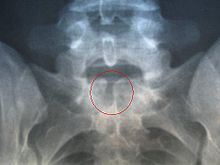

Spina bifida occulta

Il représente la forme mineure et la plus répandue de la malformation. Il n'existe pas d'ouverture ni de déformation cutanée dans la région lombo-sacrée (la peau en regard des anomalies peut rester normale ou porter une zone très poilue, un nævus ou un hémangiome, voire une petite dépression du derme). Pourtant la radio révèle une fermeture incomplète de la partie postérieure de la vertèbre. Dans cette forme, la fente reste très limitée, et la moelle épinière n'en dépasse pas (il n'y a pas de protrusion). Les conséquences de cette forme sont variables, avec en général des problèmes moteurs, et une discrète altération de la sensibilité, des atteintes du colon, voire une incontinence urinaire.